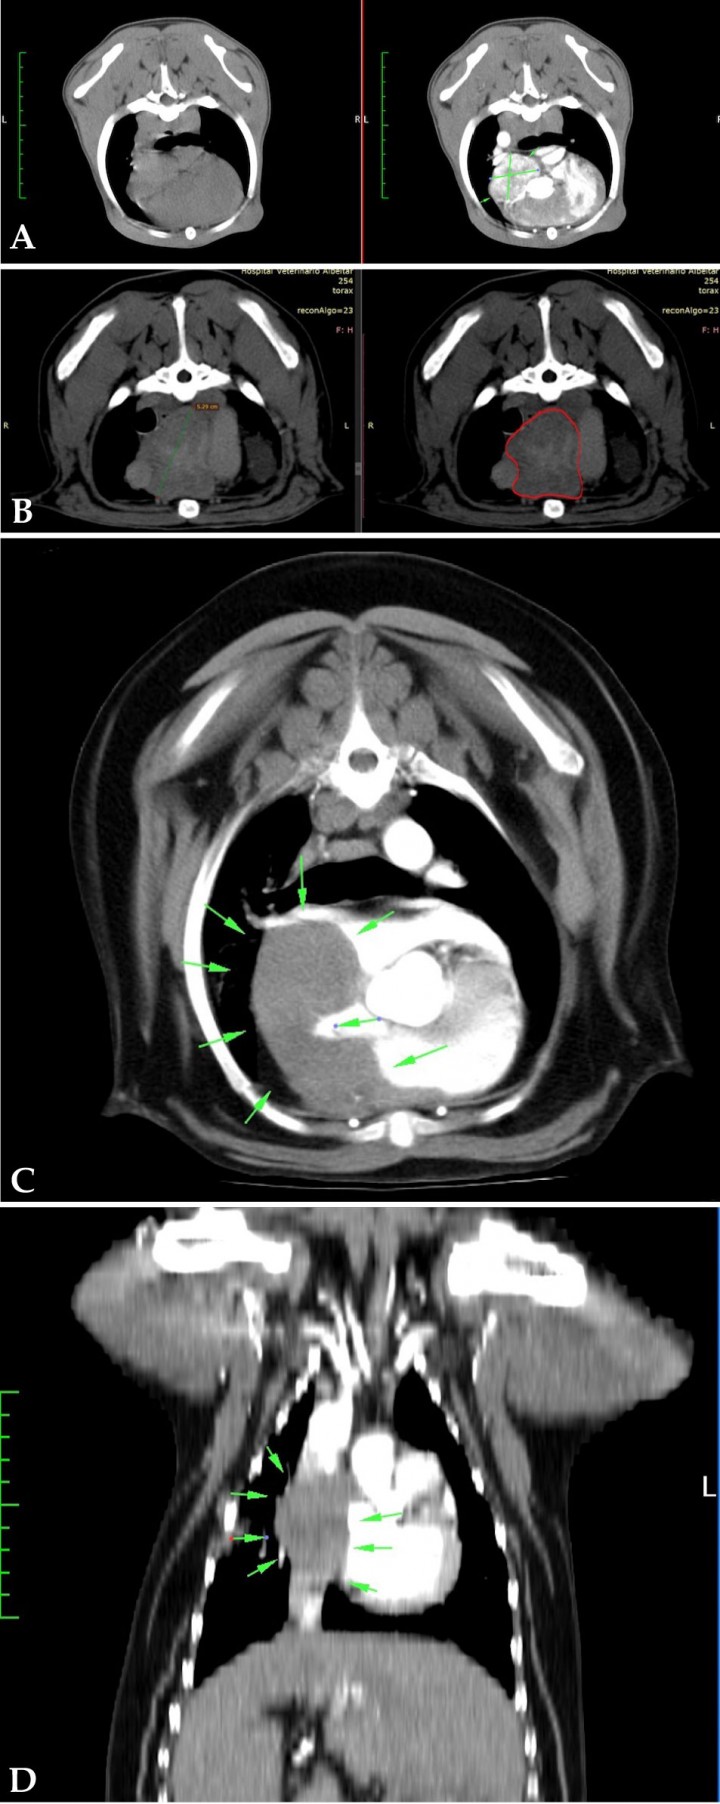

El TAC, como toda técnica diagnóstica, presenta inconvenientes como el coste o la anestesia, pero también ventajas. Algunas de sus ventajas son: localización más precisa de la masa cardiaca y, por tanto, una mejora en la planificación quirúrgica (Fig. 10).

<p>Imágenes de TAC. (<strong>A</strong>) Plano transversal tórax ventana tejido blando, precontraste (izquierda) y postcontraste (derecha). Imagen compatible con tumor de base cardiaca (entre flechas) con captación de contraste. (<strong>B</strong>) Plano transversal tórax ventana tejido blando, postcontraste (izquierda) y precontraste (derecha). Imagen compatible con tumor de base cardiaca (silueta roja) sin captación de contraste. (<strong>C</strong>) Plano transversal tórax ventana tejido blando, postcontraste. Imagen compatible con tumor de atrio derecho (entre flechas) sin captación de contraste. (<strong>D</strong>) Mismo paciente que imagen C pero en un plano dorsal. Imagen compatible con tumor de atrio derecho sin captación de contraste.</p>

Figura 10

Imágenes de TAC. (A) Plano transversal tórax ventana tejido blando, precontraste (izquierda) y postcontraste (derecha). Imagen compatible con tumor de base cardiaca (entre flechas) con captación de contraste. (B) Plano transversal tórax ventana tejido blando, postcontraste (izquierda) y precontraste (derecha). Imagen compatible con tumor de base cardiaca (silueta roja) sin captación de contraste. (C) Plano transversal tórax ventana tejido blando, postcontraste. Imagen compatible con tumor de atrio derecho (entre flechas) sin captación de contraste. (D) Mismo paciente que imagen C pero en un plano dorsal. Imagen compatible con tumor de atrio derecho sin captación de contraste.